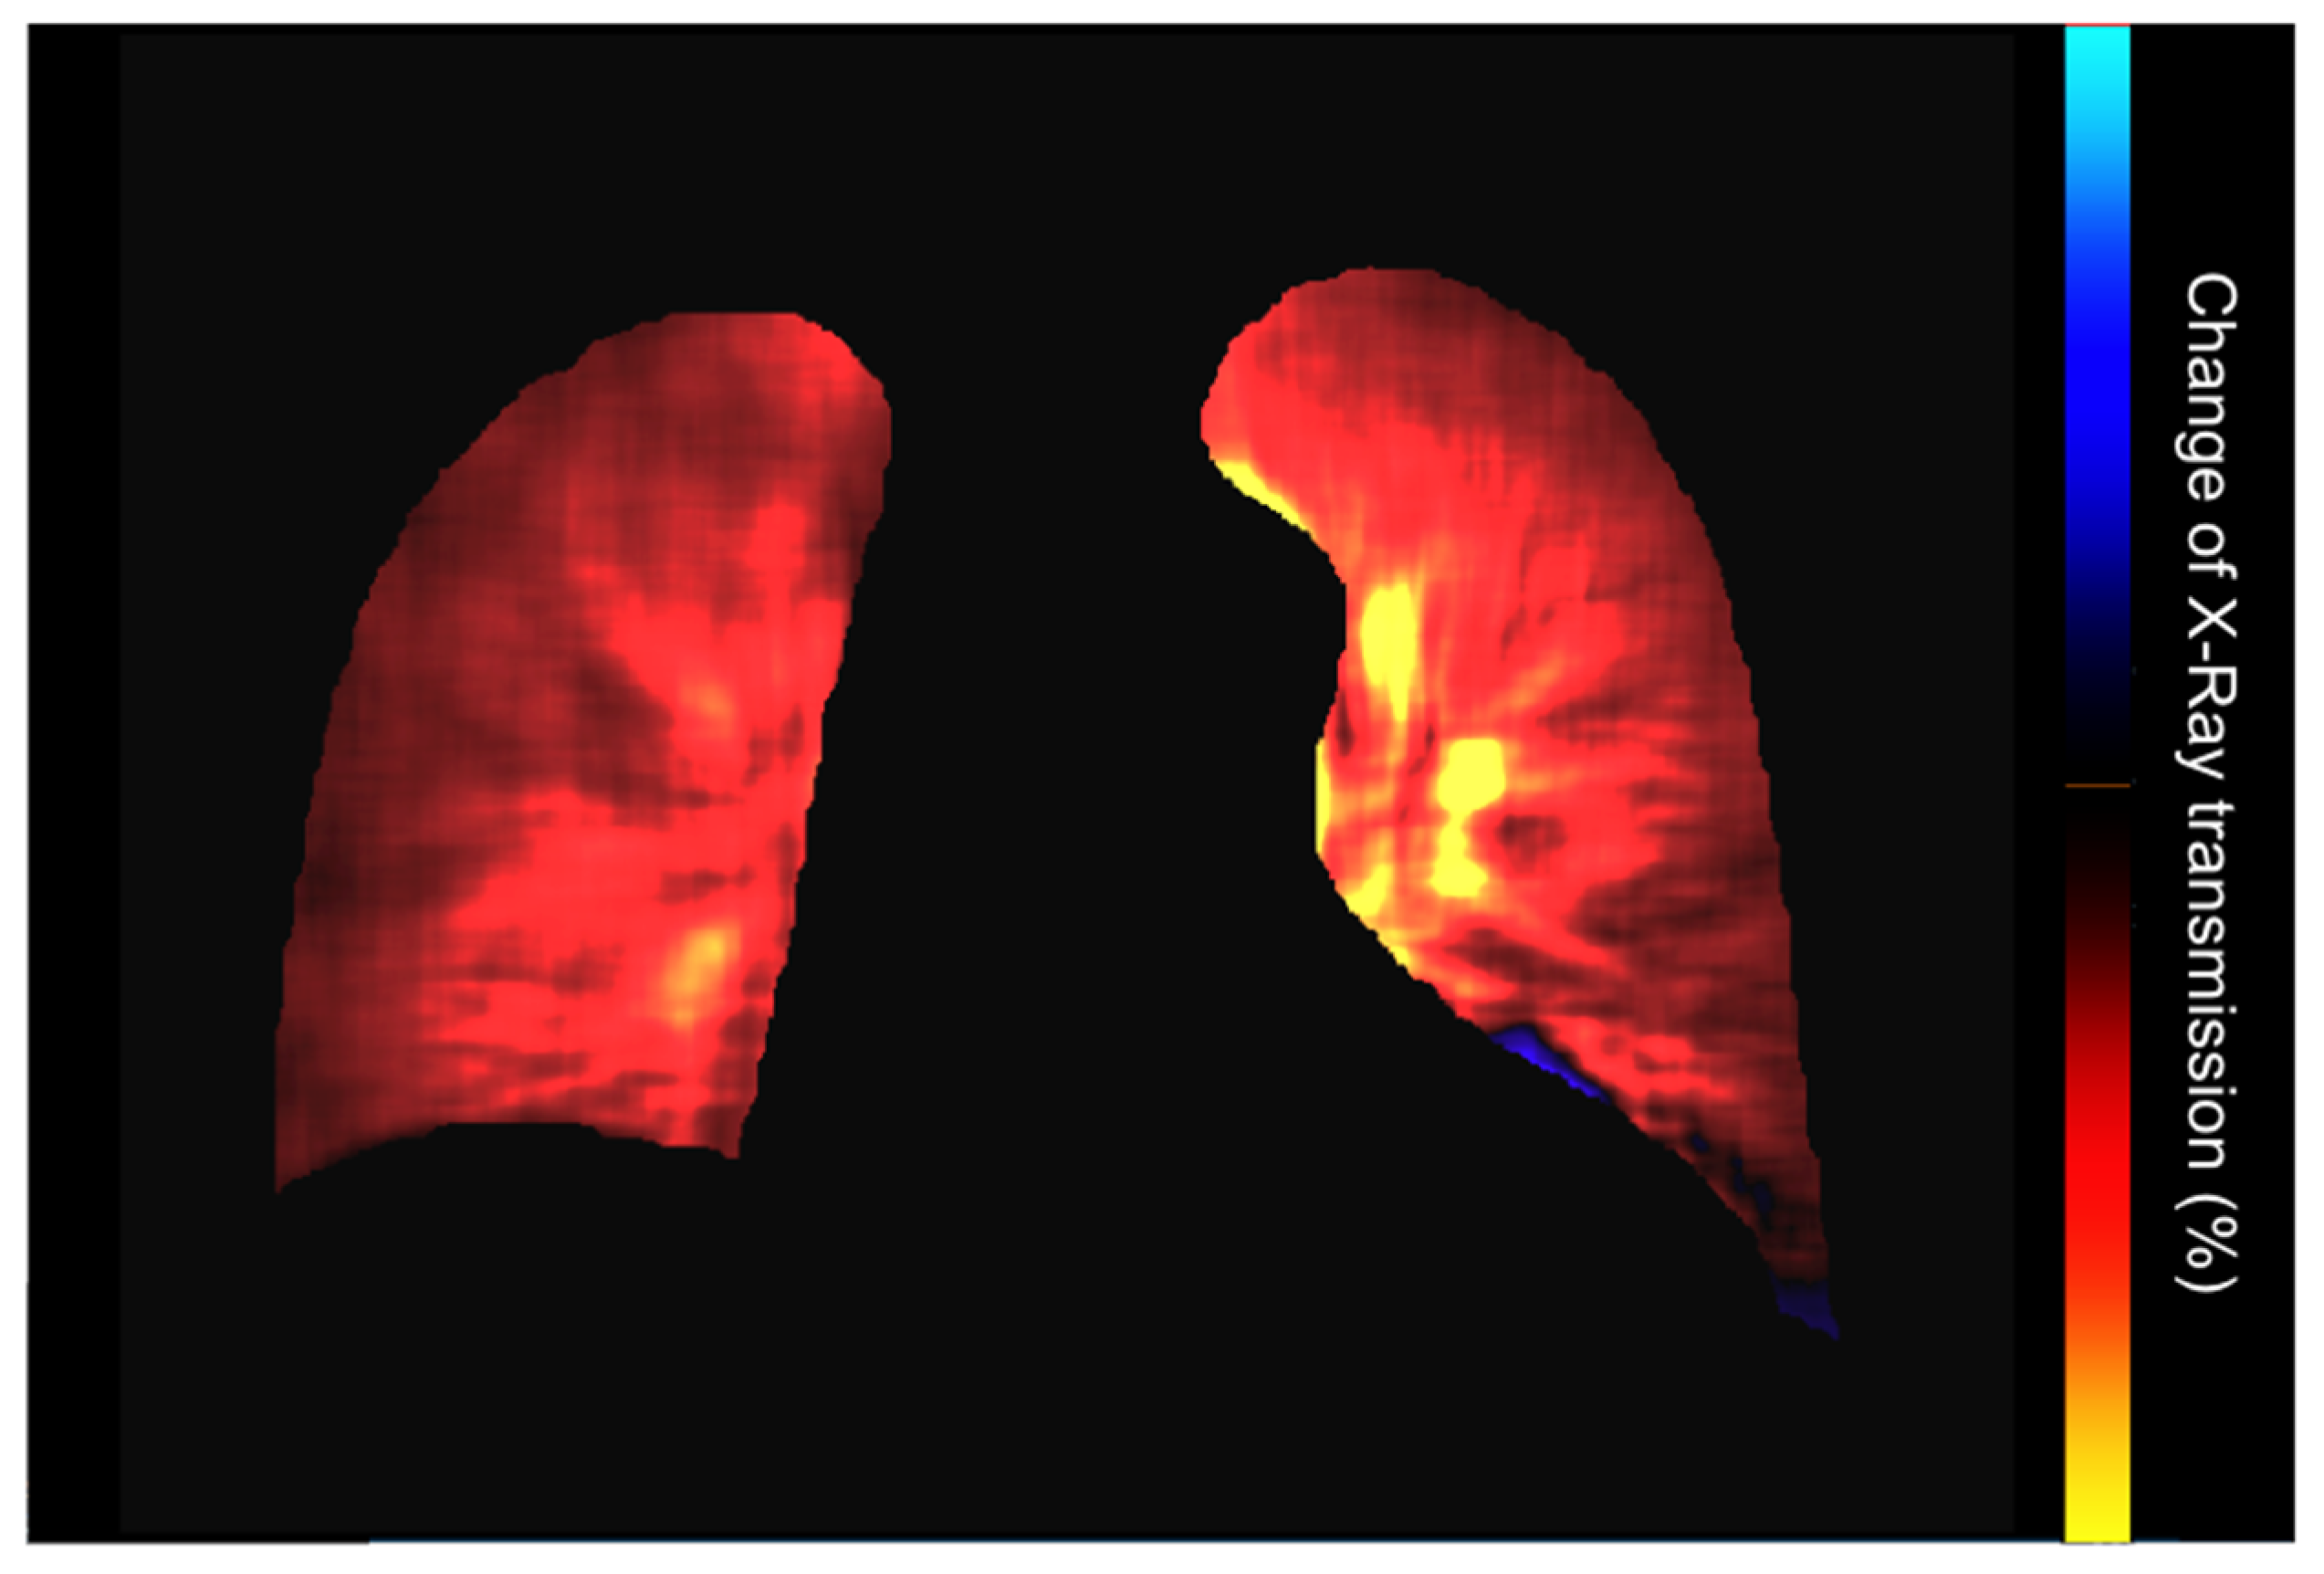

| PL-mode | Color-coded map of the lung ventilation in different areas. | Analysis of the pixel values variations during the breath cycle. | Detection of regional differences in ventilation. Useful for the follow-up of therap, especially in Intensive Care Units. |

| PH2-mode | Color-coded map representing lung perfusion. | Analysis of pixel value changes from the baseline timing (end diastolic phase). | Analysis of the pulmonary perfusion, diagnosis of pulmonary embolism. |